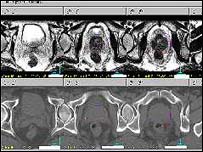

Prostat kanseri tümörünün bir resmi

Tümörün genetik taraması, tedaviyi de belirleyecek